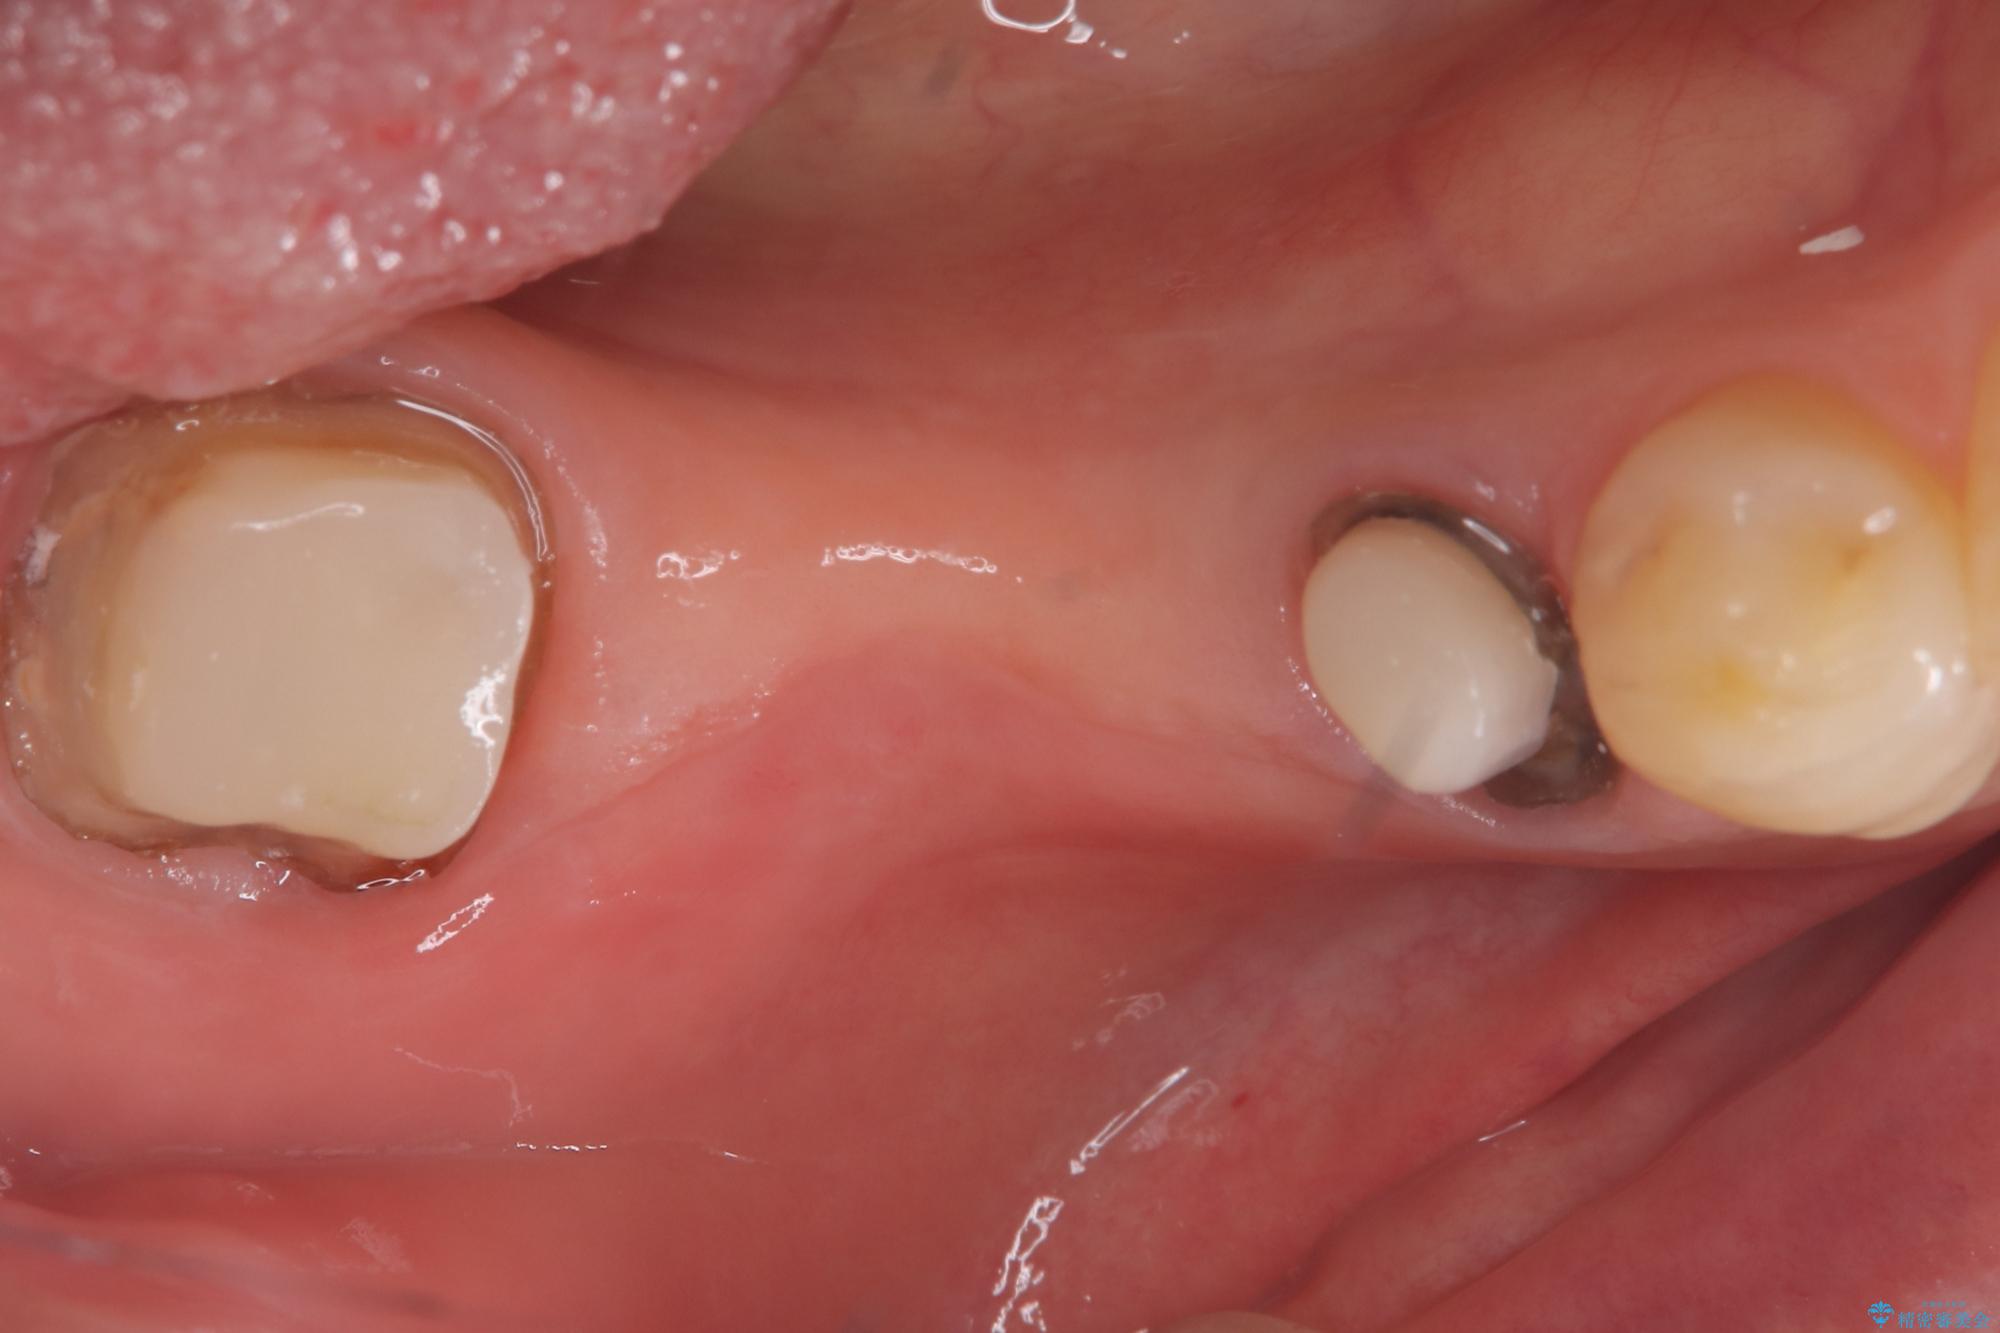

- 主訴:つい先日入れたセラミック(ジルコニア)ブリッジが奥歯部分で割れた。いつも同じ場所で壊れる。これで3度目。

セラミックに比べ、割れづらい金属(ゴールドでのブリッジのやり替えとなりました。

セラミックに比べ、破折リスクの少ない金属を使用したブリッジでのやり替えとなりました。

両支台歯が失活歯のため、どちらかもしくは両方の歯が破折した際、再度ブリッジを除去した治療が必要になるリスクとインプラント治療のご提案もさせていただきましたが、ブリッジでの治療を希望されました。

右下5番は支台歯CR築造を行っています。